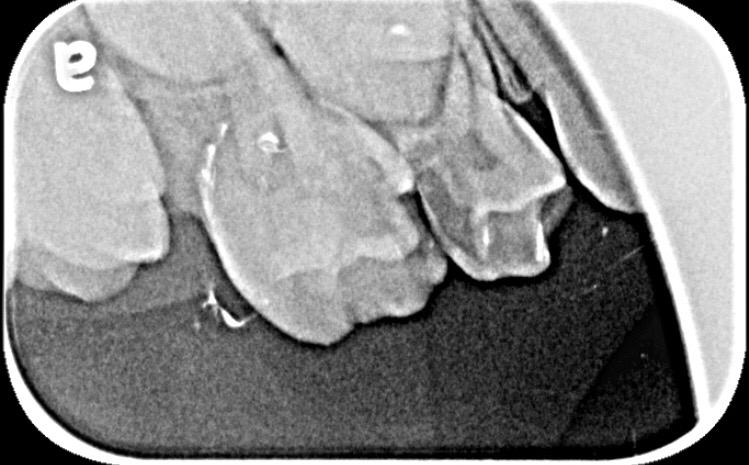

My daughter is 7 and hav deep cavity I took her to dentist one said she need 1 extraction and when I went to pediatric dentist she said she needs 4 extractions which she is going to do altogether same day I am attaching her xrays can any dentist plz advise after looking at the xrays thanks

Her both upper D are definitely for extraction and for her E need to evaluate clinically as well there might get b some Endodontic treatment and space maintainers afterwards

After extraction she will need space maintainer to keep first molar in its place so better to go for RCT to keep this tooth till age 12